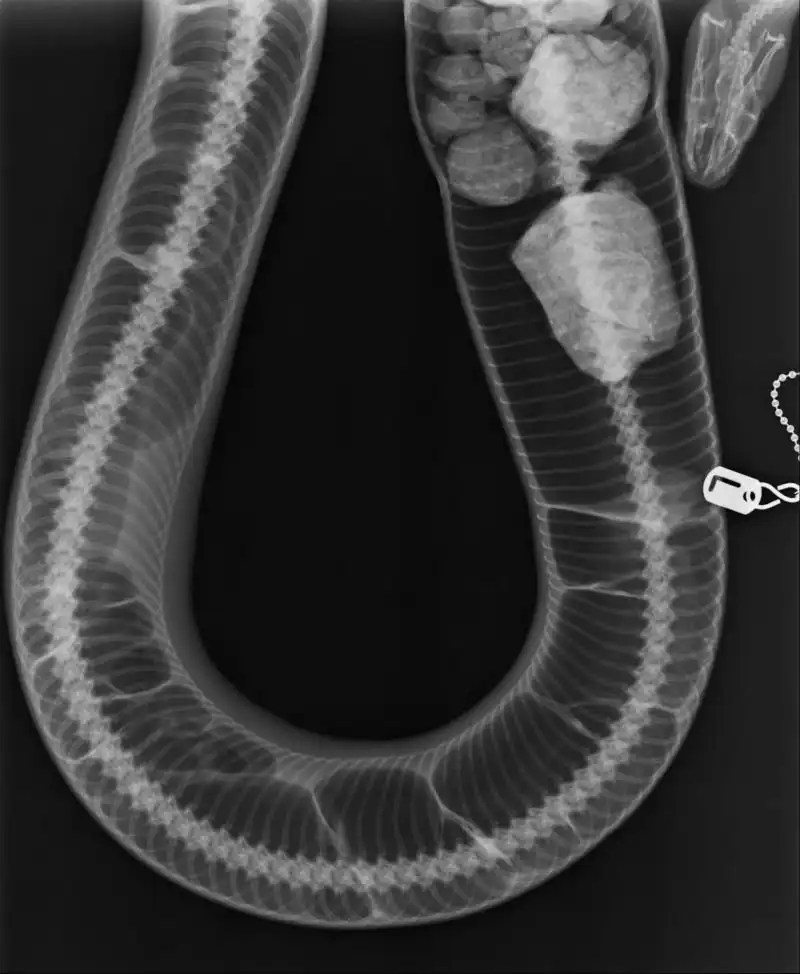

Восьмилетнего самца питона по кличке Лилл хозяин принес в ветеринарную клинику по причине того, что он не опорожнялся по-большому на протяжении года. С питанием и мочеиспусканием проблем не было, а вот дерьмо пробыло в кишечнике настолько долго, что фактически превратилось в камни.

Когда массаж и клизма не помогли, ветеринары сделали пресмыкающемуся операцию.